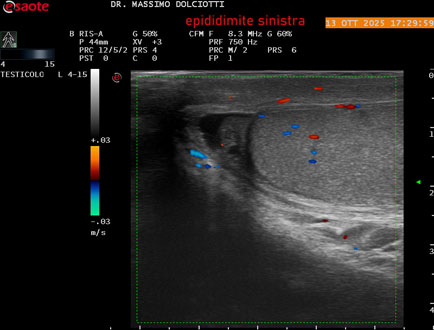

Data inserimento: 14/10/2025

Ecografia del: 13/10/2025

Strumento: Esaote MyLab Eight

Sonda: Lineare Multifrequenza 4-15 MHz

Età Paziente: M 70 anni

Motivazione dell'esame: da 2 giorni dolore al testicolo sinistro.

Commento all'esame: le immagini ed il video documentano l'epididimo sinistro spiccatamente aumentato di volume e di vascolarizzazione, come da flogosi. Didimo sinistro lievemente aumentato di volume. Quadro clinico ed ecografico da ricondurre ad epididimite acuta sinistra.

Conclusioni: epididimite acuta sinistra (acute left epididymitis).

Presentazione: Dr. Massimo Dolciotti - Ancona